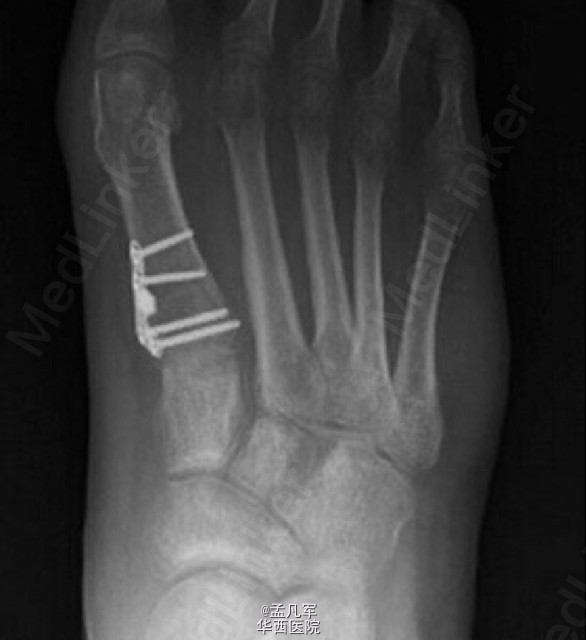

拇外翻是导致成人和青少年足部疼痛和畸形的常见原因。对不伴有严重脱位和关节炎的跖骨远端关节角异常合并跖骨近端关节面固有角增大的中、重度拇外翻畸形,第一跖骨近端截骨术或跖跗关节融合术可以有效纠正拇外翻畸形。 近端 V 形截骨术是一种常见的手术方式,可以有效的纠正角度和提高 AOFAS 评分。近端 V 形截骨术由 Sammarco 在 1929 年首次进行描述,近些年,一些学者提出应将近端 V 形截骨术联合螺钉固定与其他近端截骨方式进行对比。因为,近端 V 形截骨术在操作上存在一定的难度,并且存在一定程度的失败率。 而第一跖骨楔形截骨术可以在截骨后可以进行定制钢板固定,在稳定效果上可以更胜一寿。其操作性较 V 形截骨术更为简单。为了验证第一跖骨近端楔形截骨术与 V 形截骨术在治疗拇外翻的效果,目前 Mark 等人采取前瞻性的随机对照研究,将两者的最新研究结果发表于近期的 JBJS。该研究结果显示,在对于患者的临床结果评估上,这两种方法没有显著差异。此外,还发现第一跖骨楔形截骨术可以延长第一跖骨的长度,而 V 形截骨术正好相反,会影响第一跖骨出现短缩。跖骨近端楔形截骨术,术后跖间角从术前 14.8°±3.2°改变至术后 9.1°±2.9°(P<0.05),而 V 形截骨术使跖间角从术前 14.6°±3.9 改变至术后 11.3°±4.0°(P<0.05)。手术过程所需时间,两者相似楔形截骨术需 67.1±16.5 分钟,V 形截骨术需要花费 69.9±18.6 分钟(P=0.51)。 最终该研究者认为跖骨近端楔形截骨术与 V 形截骨术在影像学结果和术后患者疼痛、满意度以及功能上都具有可比性。值得注意的是两个截骨术,对于患肢的长度结果存在差异。因楔形截骨术在操作技术上,相对较为简单,所以临床医生采用率相对高。